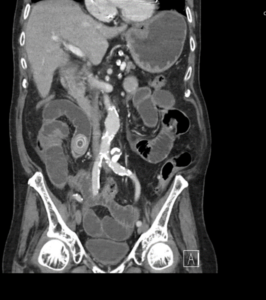

A 92-year-old man presented to emergency with abdominal pain, vomiting and fever. He had been experiencing 24 hours of abdominal pain which had become significantly worse in the last 3 hours. He has generalized abdominal tenderness and distention. Lactate is 2.5 and he has a mild AKI.

EXPLANATION -There are multiple dilated loops of small bowel secondary to small bowel obstruction. There is mild mural thickening in the right lower quadrant, suggestive of early ischemia. An abrupt transition is seen in the terminal ileum due to a 30 mm gallstone – a gallstone ileus.

Pneumobilia is present, this is secondary to a cholecystoduodenal fistula.

Gallstone ileus is an uncommon but potentially serious cause of small bowel obstruction.

- It occurs when a gallstone enters the small bowel via a biliary-enteric fistula, causing a mechanical bowel obstruction.

- The site of obstruction is the terminal ileum in 50-70% cases (as in this case), 90% of stones over 2cm in diameter cause obstruction. There may be colicky, often periumbilical, abdominal pain, distension, constipation, nausea and vomiting.

- Current surgical options are simple enterolithotomy (as in this case); enterolithotomy, cholecystectomy and fistula closure (one-stage procedure) or enterolithotomy with cholecystectomy performed later as a two-stage procedure.

- This patient went for urgent laparotomy. A 3cm gallstone was found in the distal ileum. The gallstone was able to be moved proximally, and an enterotomy was performed for removal of the gallstone via the ileum.